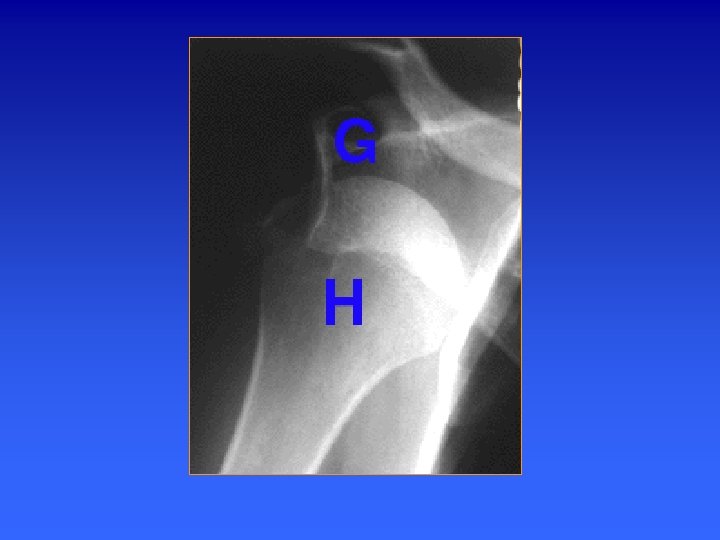

Epaule de face en rotation neutre RO Cliché indispensable devant toute épaule rhumatologique ou traumatologique. Critères de réussite: - Enfilé l’interligne gléno-huméral - Projection coracoïde sur la tête Humérale - Artic. acromio-claviculaire non dégagée - Trochiter dégagé dans l’espace supéro-externe de l’humérus 9

Epaule de face en rotation neutre RO Descriptif anatomique 1 Trochiter ( face sup dégagée) 2 Trochin (vue de face) 3 Coracoïde 4 Glène 5 Acromion 6 Clavicule 7 Espace sous acromial 8 Articulation gléno-humérale 9 bord ant de la glène 10 bord post de la glène 11 Articulation acromio- clav. 12 Gouttière bicipitale Obliquité moyenne du col anatomique 11 9 12 10

Epaule de face en rotation neutre RO La face supérieure du trochiter est dégagée avec une corticale régulière et dense (zone d'insertion du sus-épineux). Le trochin est vu de face La gouttière bicipitale se projette en situation paramédiane externe sur la tête humérale. L'interligne scapulo-huméral est déterminé par le rebord glénoïdien antérieur et le contour interne de la tête humérale. Le rebord glénoïdien postérieur plus externe que l'antérieur peut se superposer légèrement à la partie interne de la tête humérale. La portion externe de l'apophyse coracoïde se superpose avec le segment supérieur de l'interligne gléno-huméral et se superpose sur la tête humérale le pied de l'apophyse coracoïde apparaît comme une image pseudo-lacunaire Résultat